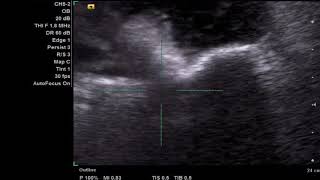

Литотрипсия - современный метод лечения почечнокаменной болезни.

Одно из наиболее часто встречающихся урологических заболеваний - почечнокаменная болезнь. Она вызывает сильные боли внизу живота, а также ...

Ударно-волновая литотрипсия (EAU - SWL RU)

Ваш врач рекомендовал вам ударно-волновое дробление камня. Во время дробления ударные волны направлены на камень и дробят его на мелкие ...